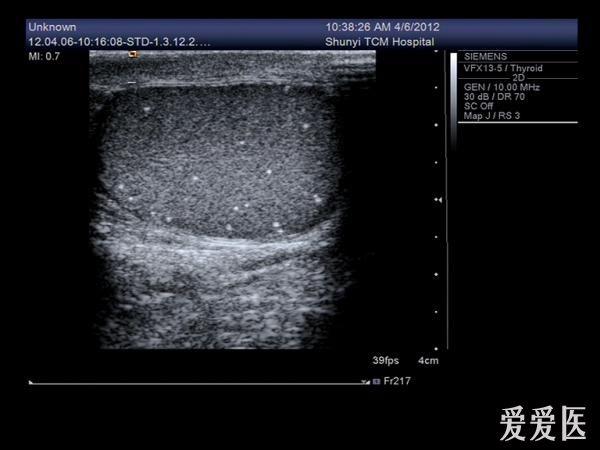

睾丸内点状强回声是什么东西?有图

前几天有个病人来检查,说睾丸疼,大小、形态都没什么变化,就是睾丸内有好多点状强回声,伴彗星尾征。请问这些东西是什么?钙化点?

典型的睾丸微石症

典型的睾丸微石症,有些人和结核有关系!